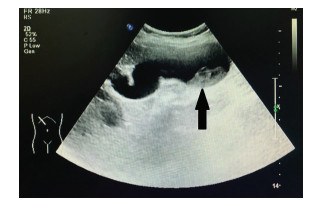

Primary fibrosarcoma of the liver misdiagnosed as hepatic abscess: A case report

Liuyang ZHU, Jiancun HOU, Long YANG, Wen TONG, Yamin ZHANG

2021, 37(7): 1665-1667. DOI: 10.3969/j.issn.1001-5256.2021.07.037

Abstract(696) HTML (210) PDF (3350KB)(42)

Abstract: